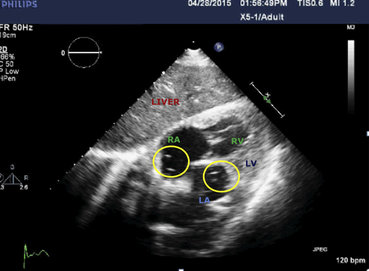

La sintomatologia del paziente è peggiorata rapidamente tanto che hanno provveduto ad un intubazione d'urgenza. Successivamente gli esami hanno mostrato la causa di quel peggioramento critico nelle ecografie e radiografia, sotto.